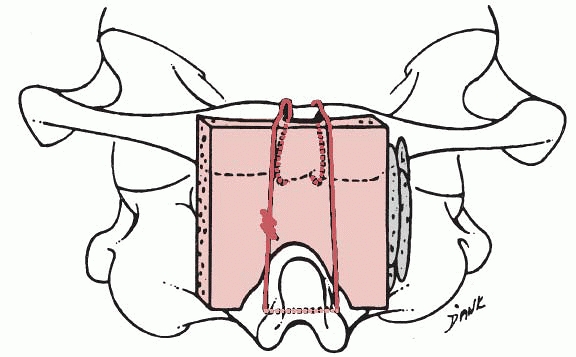

adolescents in whom the posterior elements of C1 and C2 are intact, a

triple-wire technique, as described by Wertheim and Bohlman,233 can be used (Fig. 18-25).

The wires are passed through the outer table of the skull at the

occipital protuberance. Because the transverse and superior sagittal

sinuses are cephalad to the protuberance, they are not endangered by

wire passage.

cranial skeletal traction with the patient on a turning frame or

cerebellar head rest. The patient is placed prone, and a lateral

radiograph is obtained to document proper alignment. The subcutaneous

tissues are injected with an epinephrine solution (1:500,000). A

midline incision is made extending from the external occipital

protuberance to the spine of the third cervical vertebra. The

paraspinous muscles are sharply dissected subperiosteally with a

scalpel, and a periosteal elevator is used to expose the occiput and

cervical laminae, with special care to stay in the midline to avoid the

paramedian venous plexus. At a point 2 cm above the rim of the foramen

magnum, a high-speed diamond burr is used to create a trough on either

side of the protuberance, making a ridge in the center (see Fig. 18-25A).

A towel clip is used to make a hole in this ridge through only the

outer table of bone. A 20-gauge wire is looped through the hole and

around the ridge; then another 20-gauge wire is looped around the arch

of the atlas. A third wire is passed through a hole drilled in the base

of the spinous process of the axis and around this structure, giving

three separate wires to secure the bone grafts on each side of the

spine (see Fig. 18-25B).

of premeasured length and width is removed from the posterior iliac

crest. The graft is divided horizontally into two pieces, and three

holes are drilled into each graft (see Fig. 18-25C). The occiput is decorticated and the grafts are anchored in place with the wires on both sides of the spine (see Fig. 18-25D). Additional cancellous bone is packed around and between the two grafts. The wound is closed in layers over suction drains.